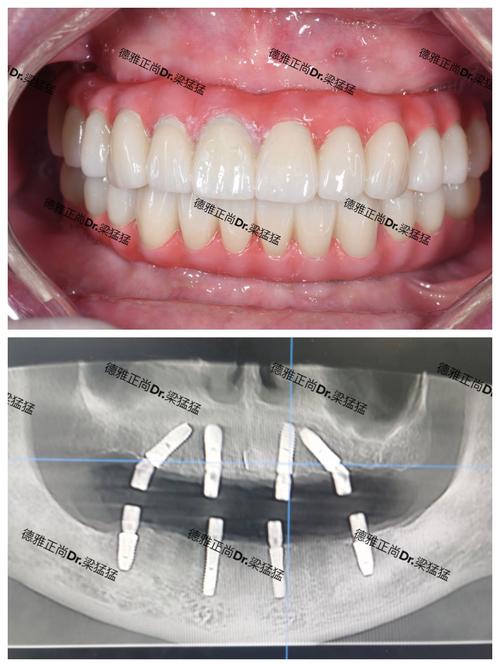

(图片来源网络,侵删)- 局部麻醉下,切开牙龈,暴露牙槽骨。

- 在预定位置、角度、深度精确植入3颗种植体。

- 根据情况决定是否同期植入愈合基台或覆盖螺丝。

- 缝合牙龈。

- 用数字化扫描或传统取模方式获取精确模型。

- 技工室根据模型制作个性化基台和全瓷牙冠。

- 试戴基台和牙冠,检查就位、咬合、接触点、美观效果。

最终戴牙:

- 粘接或螺丝固位方式将牙冠固定在种植体上。